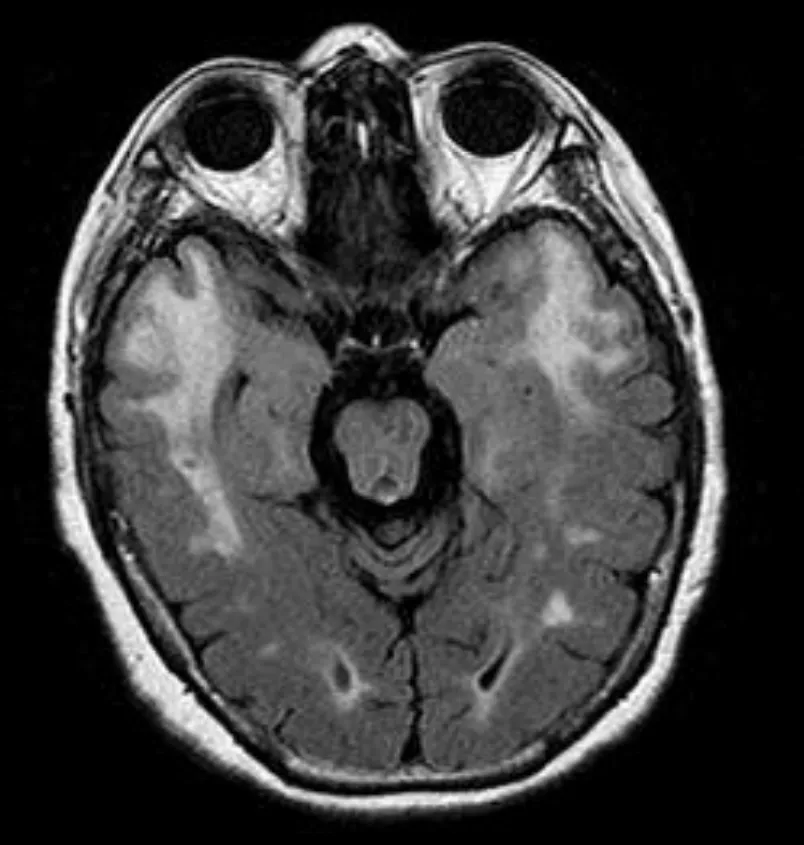

這題的解題核心在於將病患的臨床表現(年輕型中風、失智、家族史)與腦部磁振造影的典型影像特徵結合起來。圖片中腦部磁振造影(MRI)顯示的雙側顳葉極(temporal poles)和外囊(external capsules)的廣泛白質病變,是診斷 CADASIL 最關鍵的視覺線索。